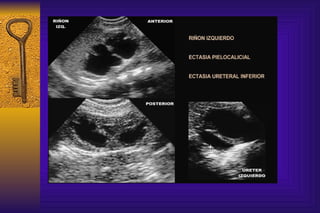

Como detectamos anormalidades de los riñones o de las vías urinarias La ecografia renal permite identificar la morfología renal  y es útil para establecer calidad de las vías urinarias. Permite observar cálices y la pelvis pudiendo medir los diámetros anteroposteriores y espesor del parénquima

Como detectamos anormalidadesde los riñones o de las vías urinarias La ecografia renal permite identificar la morfología renal y es útil para establecer calidad de las vías urinarias. Permite observar cálices y la pelvis pudiendo medir los diámetros anteroposteriores y espesor del parénquima